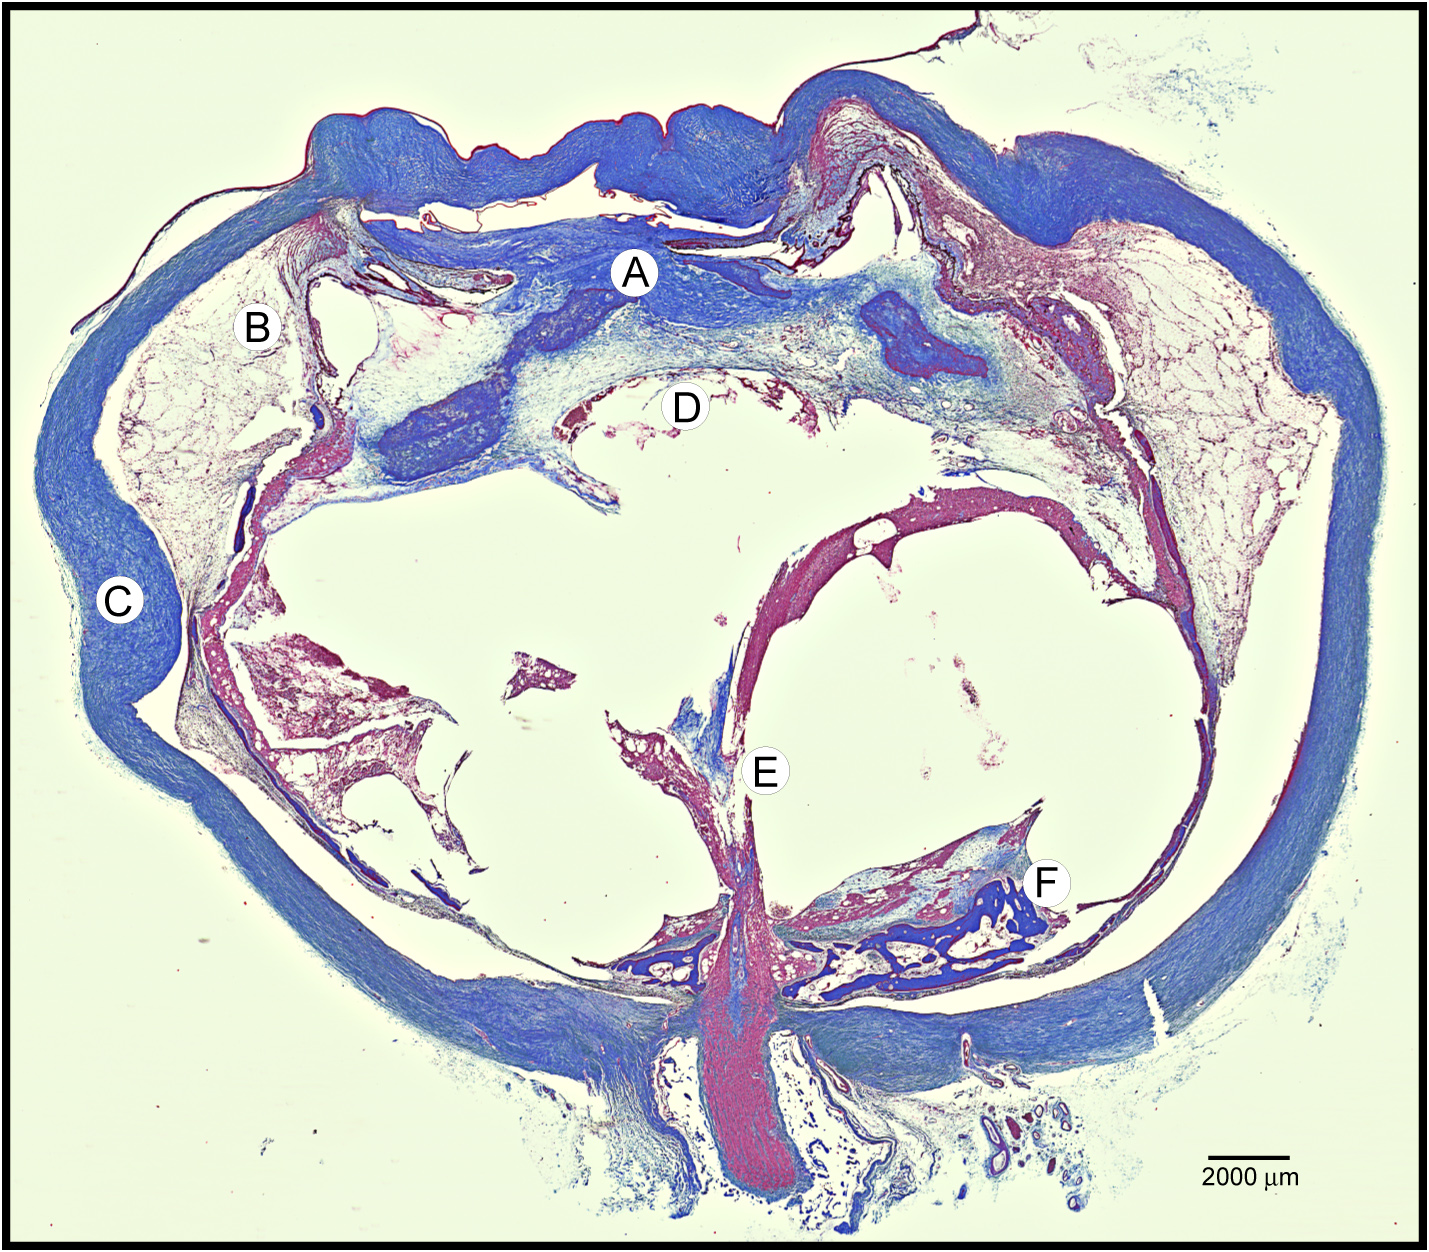

Figure 2. Masson’s trichrome stain of

autosomal dominant neovascular inflammatory vitreoretinopathy (ADNIV)

eye demonstrates fibrovascular proliferation and features of phthisis. A:

There

was massive fibrovascular connective tissue within the pupil,

overlying the iris, and causing detachment of the ciliary body. B:

A

supraciliary effusion was present outside the detached ciliary body. C:

The

sclera was thickened. D: There were a few lens remnants

present. E: A fibrovascular stalk extended from the optic nerve

to the peripheral retina. F: The retina was detached, atrophic,

and osseous metaplasia was present.